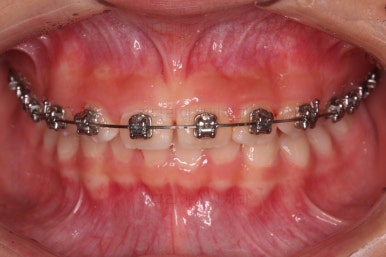

과개교합, 옥니, 앵글씨 2급 부정교합 모두 좋아지고 있어요.

마무리를 해줍니다.

앞니 각도가 매우 좋아졌고요.(옥니 개선) 위 아래 앞니가 덮는 정도도 개선되었어요.(과개교합, 딥바이트)

엉성했던 어금니 맞물림도 매우 좋아졌어요.(앵글씨 2급 부정교합)

부산교정병원 전후사진을 비교해 볼게요.

협조도가 요구되는 장치를 잘 못끼는 바람에 중간에 우여곡절이 있었고 힘든 과정도 있었지만 비교적 만족스러운 치료를 할 수 있었어요.